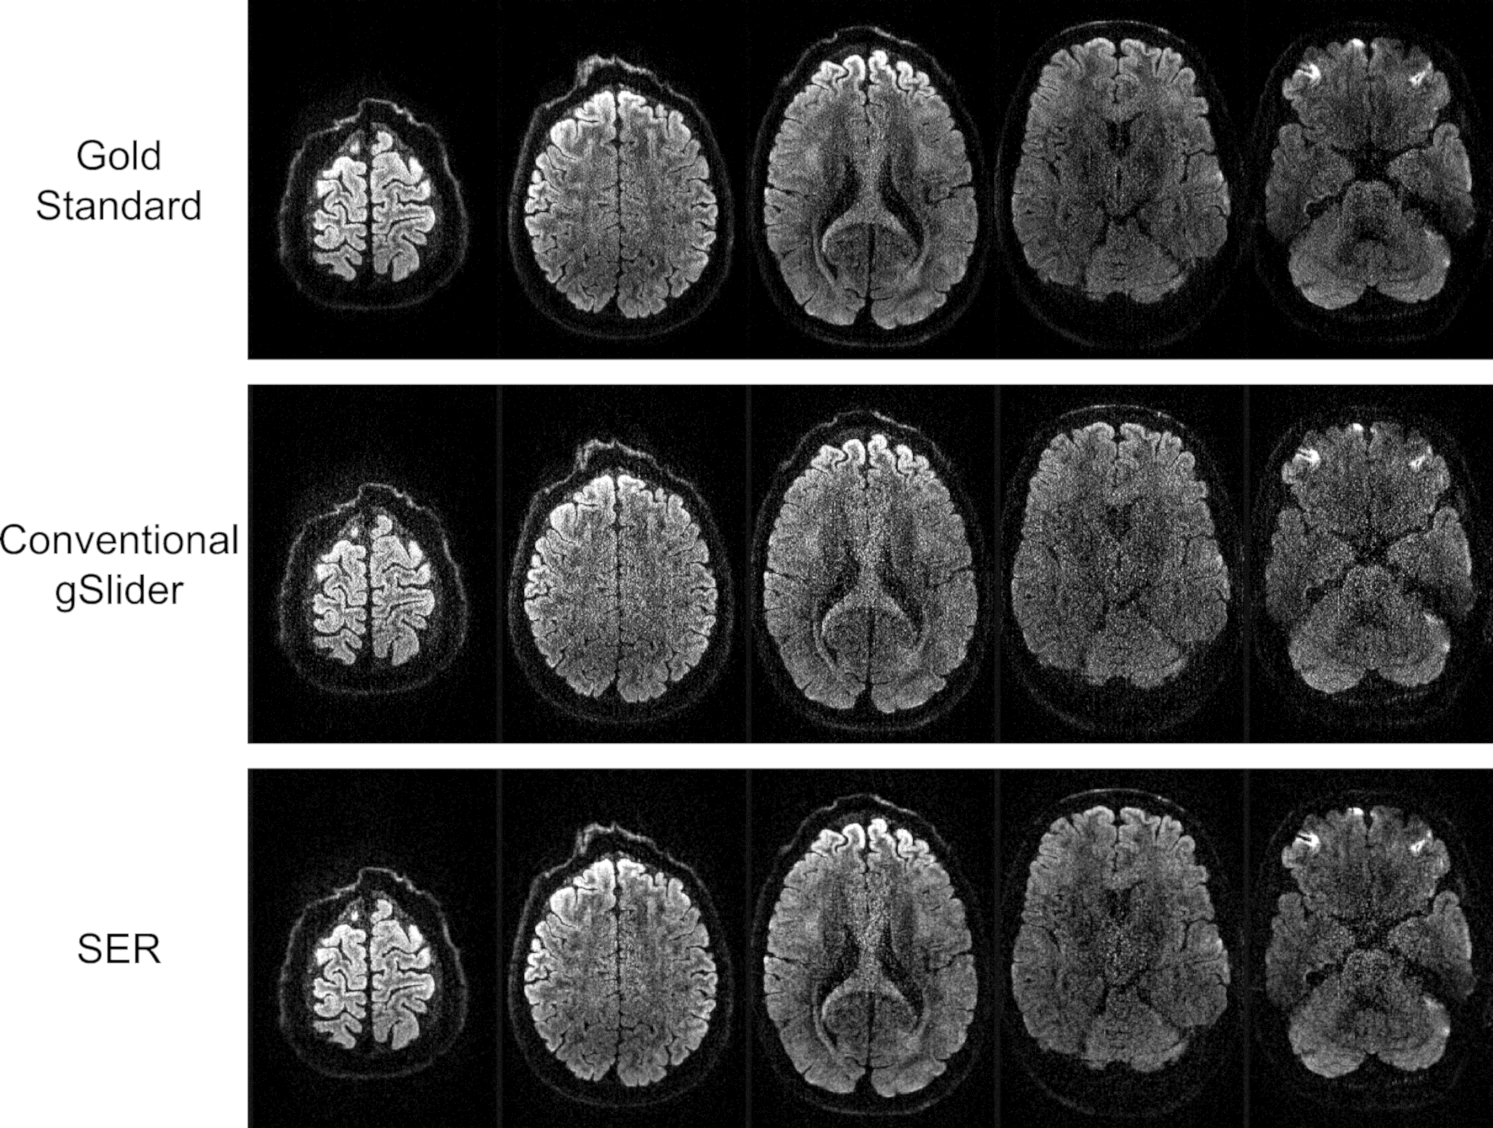

Gold standard, conventional gSlider, and SER images from several slices of a representative DWI are illustrated in Fig.Β 2. As can be seen, the conventional gSlider result has a noisy appearance, particularly near the center of the brain. On the other hand, the SER has a much less noisy appearance, as should be expected.

Figure 2: Gold standard, conventional gSlider, and SER images from five slices of a representative DWI.

More detail is available from inspecting the zoomed-in images presented in Fig.Β 3, which also includes comparisons against MPPCA, LPCA, and GPCA. From this figure, it can be observed that all four denoising approaches have an apparent reduction in noise, although the extent of this varies from method to method. MPPCA appears to have the least amount of noise reduction among the four, while both GPCA and LPCA produce very crisp-looking images with minimal obvious noise content. We would argue that the SER result does not look as crisp or cosmetically pleasing as the LPCA and GPCA results, although still represents an improvement over MPPCA.

Figure 3: Comparison of a slice from a representative DWI obtained by different reconstruction and denoising approaches. Zoomed-in images (from the region corresponding to the yellow box shown in the gold standard image) are also shown for easier visualization of fine image details.